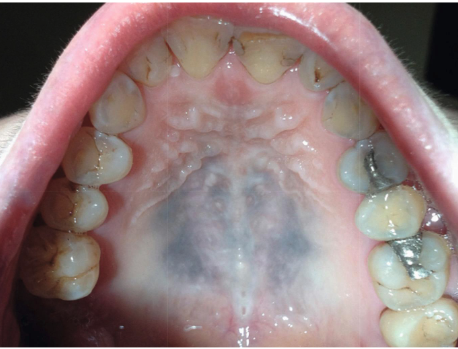

what is this

amalgam tattoo